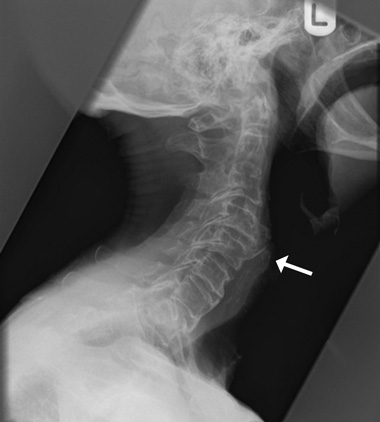

A 79-year-old man presented with painless dysphagia. Results of an oesophagogastroduodenoscopy were unremarkable. A dynamic videofluoroscopic examination was diagnostic, revealing hypertrophic cervical osteophytes indenting the hypopharynx and oesophagus. The osteophytes were also seen on a lateral cervical spine radiograph (Box). The dysphagia responded to dietary modification.

Although cervical osteophytes are seen in 20%–30% of the geriatric population, they are an unusual (and treatable) cause of dysphagia. Dysphagia occurs because of mechanical blockage as well as inflammation of the peripharyngeal and peri-oesophageal tissue. As enlarged cervical osteophytes may be an incidental finding, it is important to exclude other potential causes, such as neoplasm.1,2